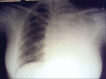

Uterine sarcomas are rare and represent approximately 3.2% of all invasive uterine cancers. The annual incidence rate is less than two per 100,000 women. The median age at which uterine sarcoma diagnosed is 56 years. The most common histologic pattern is leiomyosarcoma (LMS) which originates from the myometrium or myometrial vessels. Uterine LMSs are aggressive tumors with high rates of recurrence. The most common mode of spread is hematogenous, with lymphatic spread being rare. Recurrences of up to 70% are reported in stage I and II disease with the site of recurrence being distal, most commonly the lungs or the upper abdomen. But the intra bronchial spread is extremely rare. Here we are reporting a case of uterine LMS with endobronchial metastasis causing whole lung collapse.